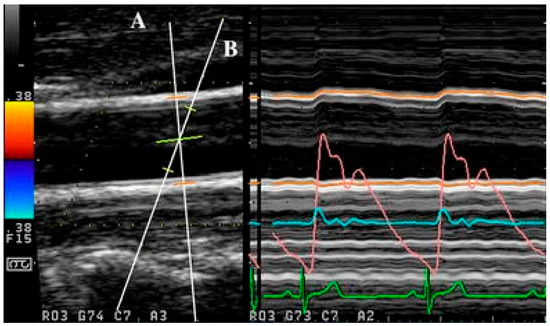

Simultaneous acquisition of diameter and velocity data is technically more complex than non-simultaneous acquisition owing to the need for acquisition of both the velocity and diameter at the same transducer angle. This has been explored in studies seeking to overcome alignment errors.

For instance, a method utilised in [33,104,153] employed M-mode for diameter measurement and PW Doppler for velocity measurement. In these studies, prior to data acquisition, the transducer was positioned longitudinally in B-mode while ensuring that the vessel walls were clearly delineated. The Doppler angle used was near optimal at 58 to 60 degrees and the Doppler gating was adjusted in B-mode as well. Subsequently, during measurement, a split screen was used to obtain both diameter and velocity data at a sampling frequency of 1000 Hz. Although this method allows for automatic acquisition of the data simultaneously via the split screens, the gates and angles still need to be adjusted manually, which may affect the signals, particularly in the derivative calculations used to obtain the PWV from the lnDU loop [33,104]. This method was also used in separate research that tested a position near the aortic arch, wherein 10-beat cine loops were used in M-mode and PW Doppler imaging. Kowalski et al. [153] further introduced the use of a fluid-filled phantom between a probe and vessel which acted as an intermediate medium to prevent external pressure from the transducer from distorting the aortic wall motion.

Simultaneous acquisition, as proposed in [5], may also be conducted with constant perpendicular placement of the ultrasound transducer via the perpendicular ultrasound velocimetry (PUV) technique. In this technique, the velocity is not obtained via Doppler ultrasound but rather via cross-correlation techniques. The principle for measurement is akin to particle imaging velocimetry (PIV) [154] and PUV uses 2D cross-correlation in the time domain on raw RF data to determine the axial velocity distribution of the flow. In PUV, the ultrasound system is operated in fast B-mode or multiple M-line mode. According to Beulen et al. [5], the perpendicular placement allows for accurate and simultaneous assessment of diameter and velocity without the need to account for angle correction.